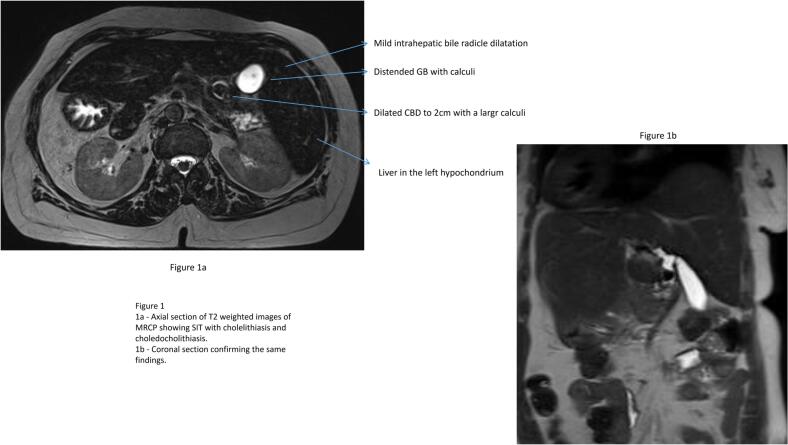

An ultrasonogram abdomen revealed liver in the left hypochondriac and epigastric region with normal echoes and no focal lesions, Gall bladder calculi of 1 cm with normal wall thickness and sonographic positive Murphy’s sign. The common bile duct could not be visualised due to excessive bowel gas. An MRCP revealed features of situs inversus with distended gall bladder with large calculus of 1.5 cm and dilated CBD of 2 cm with mid CBD calculus of 1.8 cm with dilated intra hepatic biliary radicles (Fig. 1). She was eventually diagnosed with situs inversus totalis, cholecystolithiasis, and choledocholithiasis with obstructive jaundice in cholangitis. In view of the cholangitis, she received parenteral antibiotics and was planned for ERC, stone retrieval and biliary stenting. However, ERC was attempted and failed twice due to altered duodenal anatomy and difficult manipulation. Subsequently, she was referred to our team of Surgical Gastroenterology and a decision for surgical intervention was made.